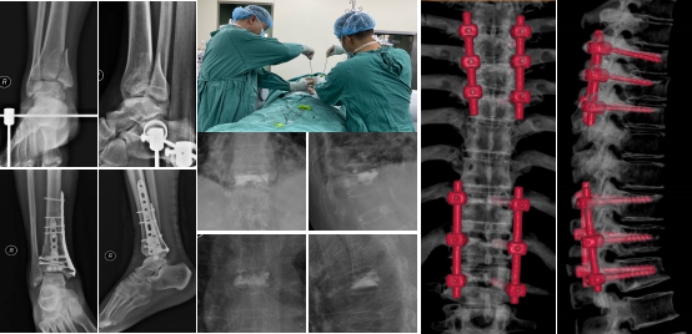

在医学的道路上,永不停歇学习是对患者健康的保障。近日,市第一人民医院医联体成员单位——青川县第一人民医院主治医师肖寒在我院脊柱创伤科完成了8个月的进修学习,收获了满满的知识与技能,荣获科室“优秀进修医”称号肖寒医生将新的医疗技术和理念带回基层服务更多的基层群众。

在脊柱创伤带教老师的指导下,肖寒医生积极参与各种病例讨论,学习先进医疗设备操作,深入学习脊柱创伤领域最新治疗技术,熟练掌握胸腰椎骨折、老年骨质疏松性椎体压缩骨折、四肢常见骨折等治疗技术